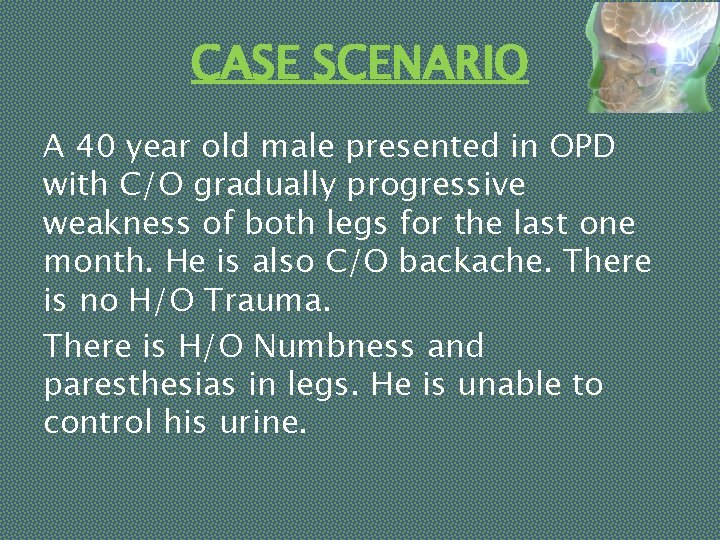

CASE SCENARIO A 40 year old male presented in OPD with C/O gradually progressive weakness of both legs for the last one month. He is also C/O backache. There is no H/O Trauma. There is H/O Numbness and paresthesias in legs. He is unable to control his urine.

CASE SCENARIO On Examination Pulse is 84/min (regular), BP: 180/105 mm Hg. Bulk is normal in both legs Tone is increased in both legs, Power is 3/5 in right leg and 2/5 in left leg. Knee and Ankle Reflexex are Brisk bilaterally. Both Planters are upgoing. Ankle Clonus is present on both sides. Upper limbs are normal. Tenderness at back of chest. What is your Diagnosis? ?

This patient has SPASTIC PARAPLEGIA (Lesion) at T 10 spinal level due to Cord compression (aetiology). It is complicated by bladder involvement (functional status)